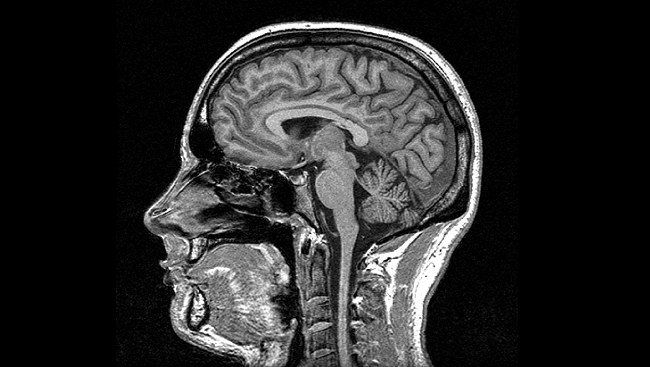

Magnetic Resonance Imaging

(MRI)

- Uses a magnetic field and pulses of radio wave energy to make pictures

- Used to detect tumors, bleeding, injury, blood vessel disease, or infection

- The best tool to detect a stroke

- Most expensive imaging study

- Must remove all metal prior to exam